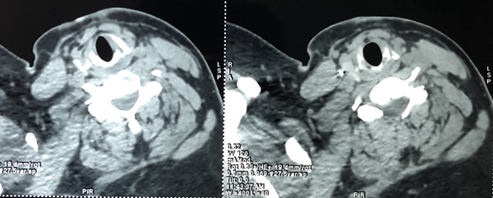

A cervico-thoracic CT-scan was done objectifying, in addition to multiple

subcutaneous metallic foreign bodies (Figure

2), a metallic wire which has migrated in the supra clavicular area and

reached the carotid region, between the internal carotid artery and the

internal jugular vein and reaching the upper part of the thorax, measuring

approximately 4cm (Figure 3).

Figure

3: Cervical CT-scan –

cross section showing cervico-thoracic steel wires embedded between the

internal carotid artery and the internal jugular vein